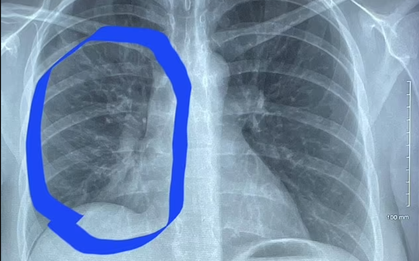

Nữ sinh chuẩn bị bước vào năm cuối cấp 3, bất ngờ rơi vào cảnh nguy kịch vì hệ thống miễn dịch rối loạn, đồng thời mắc viêm mạch hệ thống, lupus ban đỏ và huyết khối vi mạch - ba căn bệnh tự miễn cực hiếm, khiến cả phổi, thận đều suy, tính mạng chỉ tính bằng giờ.